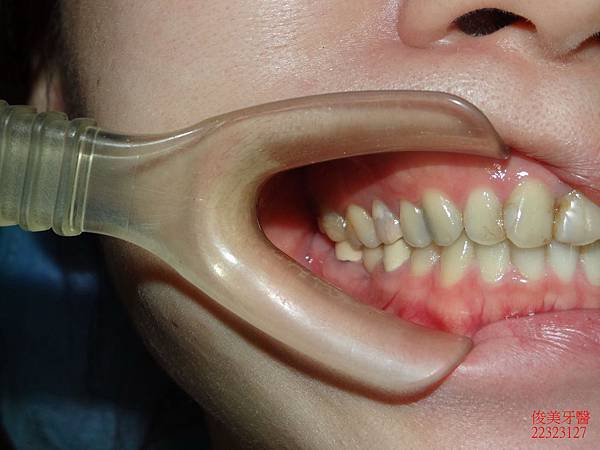

側邊咬合。

上排牙齒已有延長的現象,牙縫更容易塞東西,且沒有咀嚼功能。

之前已將右側智齒拔除,僅留左側供咀嚼。